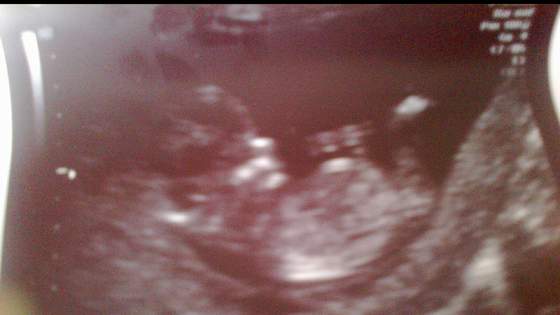

Ginowi ciężko było uwierzyć, że już czuję ruchy, ale stwierdził, że przecież ja wiem lepiej

No i zerkamy na płeć (of kors nic nie mówiłam, że tydzień temu byłam gdzie indziej i lekarka sugerowała, że to mógłby być chłopiec). A gin mówi, że na 95% dziewczynka

No i rzeczywiście, już żadnego cypelka nie widać!!! A podobieństwo tego obrazu do tego jak dowiedzieliśmy się w I ciąży, że będzie dziewczynka uderzające!!! Wow, ale byłoby super! Szczególnie, że marzyliśmy o drugiej dziewczynce.